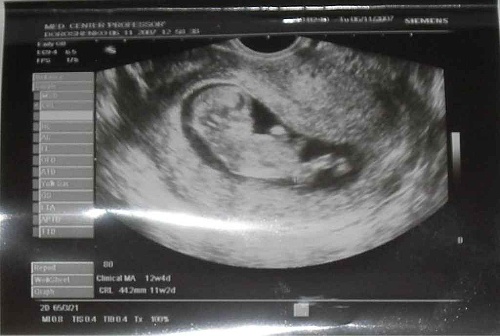

Второй раз проводится первое плановое ультразвуковое исследование. Термин «плановое» подразумевает проведение диагностики в установленные сроки, которые являются общепринятыми на данный момент времени. Делают 2-ое УЗИ на сроке примерно 10-12 недель. Его основная цель – убедиться в благополучном течение беременности, а так же удостовериться нормальном развитии плода и определить наличие некоторых патологий, в том числе и тех, которые носят генетический характер (например, синдром Дауна).

- Пороки развития плода. Например, для диагностики синдрома Дауна врач оценивает толщину воротникового пространства и визуализацию и длину носовой кости, длину бедра При УЗИ на ранних сроках беременности также можно выявить пороки развития внутренних органов и нервной системы.

Для первого скринингового исследования эти дни включают промежуток с 12 нед. 2 дня до 12 нед. 4 дня. Именно в этом интервале плод уже достаточно вырос для оценки самых маленьких органов (хрусталики глаз, сердце), и вероятность констатации наиболее важных морфологических изменений значимо выше, нежели в 11 недель 0 дней. С другой стороны, каждый прожитый малышом день увеличивает не только рост и массу тела, но качество картинки на аппарате УЗИ.

- длина зародыша или копчико-теменной размер (КТР);

- размеры головки (бипариетальный диаметр, окружность, длина ото лба и до затылка);

- симметрия полушарий мозга;

- наличие/отсутствие ряда структур мозга, обязательных для данного срока беременности.